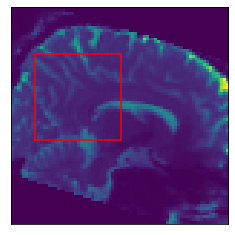

Inference stage. Now we present results of the inference stage with two DW-MRI real datasets. First, the free access dataset Stanford HARDI (Rokem et al., 2015) included in DIPY Library, with dimension (81,106,76) voxels and 160 signals per voxel (number of gradients). The acquisition protocol composed uses 150150150 gradients with b-value equal 200020002000 and 101010 with b-value equal zero. Second, a local DW-MRI with (128,128,70)12812870\left(128,128,70\right) voxels with 646464 gradients with b-value 100010001000 plus 111 gradient with b-value 00, each of them is repeated 555 times resulting in signals of size 325325325. Training time for our models by depends on datasets: The Voxel model takes 1.24sec.1.24𝑠𝑒𝑐1.24sec. for the Stanford HARDI and 1.24sec.1.24𝑠𝑒𝑐1.24sec. for out local dataset. Meanwhile, Neighborhood model takes 1.91sec.1.91𝑠𝑒𝑐1.91sec. for the Stanford HARDI and 3.34sec.3.34𝑠𝑒𝑐3.34sec. for our local dataset. Prediction times are shown in Table 1. Figure 7 compares the final results in a Stanford dataset slice, showing the local detected structure with the studied models. More slices results are presented in Appendix C.

Refer to caption

(a) DW-MRI

(b) Slice Zoom

Figure 7: Predicted intravoxel structure in real data with the compared models.